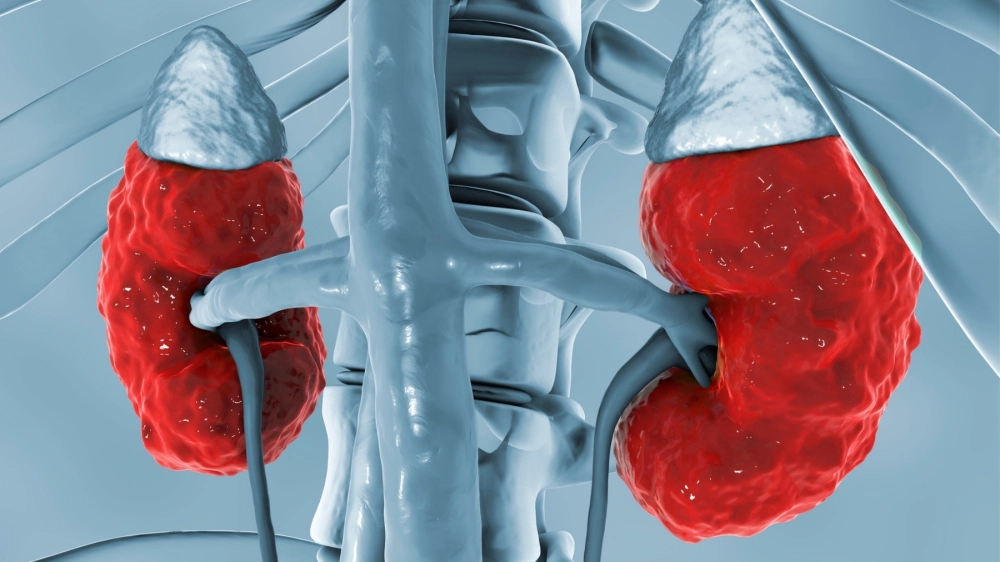

Cấu trúc cầu thận bị tổn thương